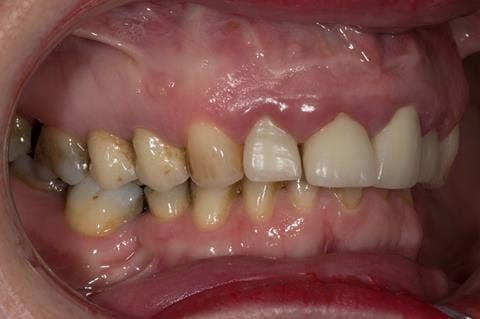

Provision of a maxillary cobalt chromium based partial denture/protective occlusal splint in a heavily restored dentition

- High smile line showing gum above gingival zeniths of upper front teeth when smiling. Aesthetic failure of the upper four incisors with inflammation of the gingivae and mis-match of the gingival zenith levels.

- Other than the maxillary incisors the remaining dentition was in marginally better condition being moderately to heavily restored. Many will probably require replacement and restoration from time to time mainly from wear and tear owing to occlusal forces.

Following consultation and second discussion appointment the patient chose to have option 3 namely, a maxillary cobalt chromium based partial denture/protective occlusal splint. The clinical situation and treatment process is shown in detail below with photographs. The patient was successfully rehabilitated with this and her quality of life considerably improved. The clinical work was provided by Finlay and the technical work by Rowan.